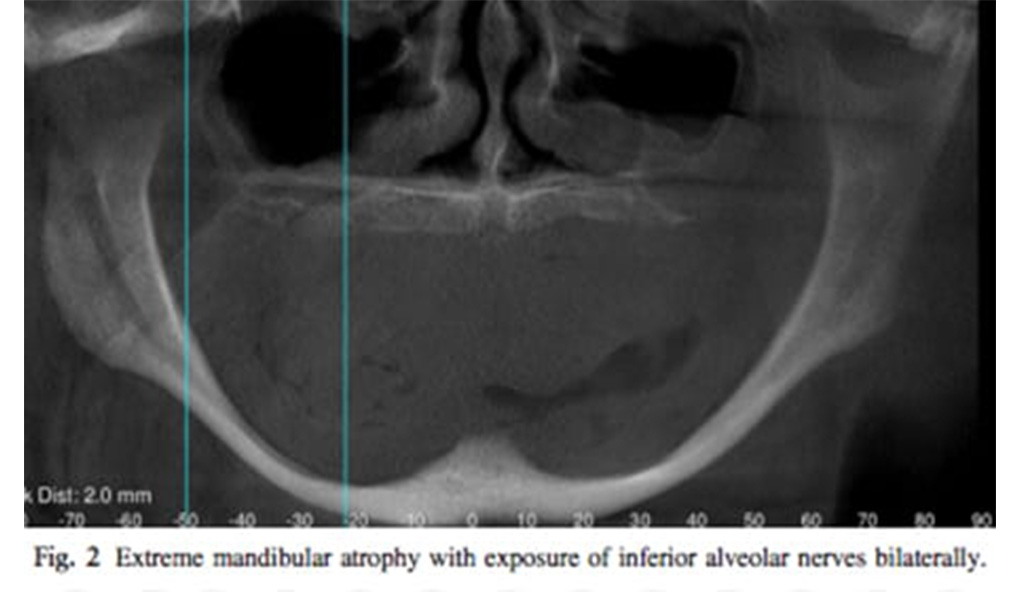

The atrophic and edentulous jaw can pose a number of challenges for the implant clinician. In simple terms, the amount of bone that remains is insufficient for the conventional placement of a dental implant. A variety of treatment strategies can be employed to enable implants to be placed despite the paucity of bone stock in either the mandible or the maxilla. Conceptually these strategies follow one of two pathways: either augmentation of the bone, or the novel utilization of the remaining bone. This article will discuss patient assessment, treatment planning, and the range of contemporary options available to enable fixed implant based rehabilitation of each jaw. “The edentulous patient is an amputee, an oral invalid, to whom we should pay total respect and rehabilitation ambitions” (P-I Branemark, September 2005).